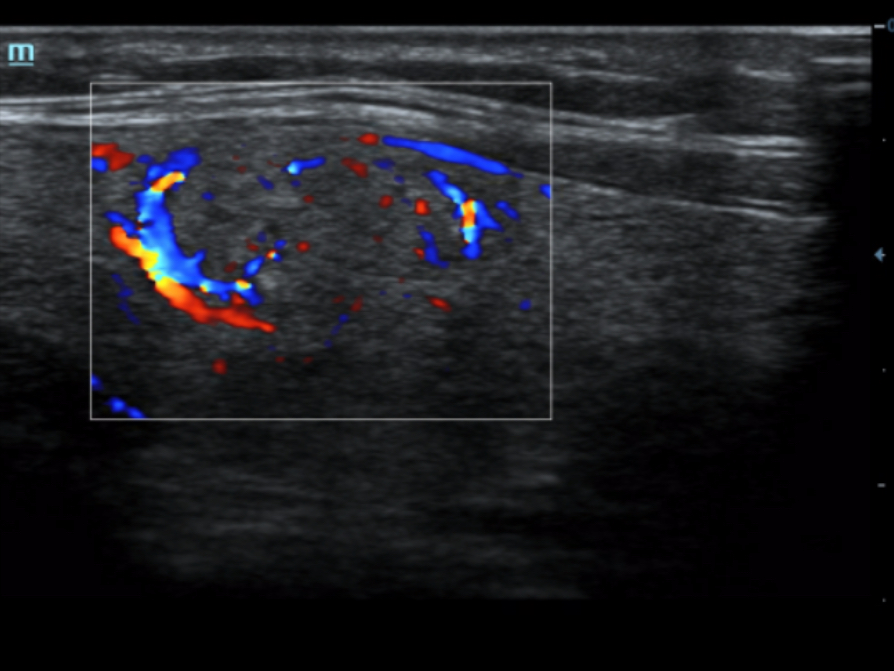

An innovative technology to better visualize tiny vessels and complex flow patterns, based on Mindray's exclusive processing algorithm.